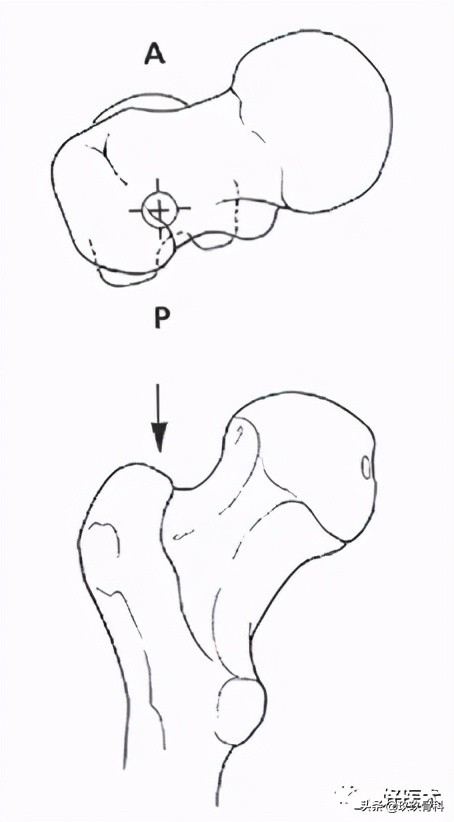

1)顺行股骨髓内钉进针点

部位:

- 梨状窝

- 梨状窝后外侧

2)顺行股骨髓内钉进针点的准备

- 髋关节屈曲内收

- 大粗隆近端纵切口(不能太靠后)

- 安放导针

- 安放软组织保护挡板

3)逆行股骨髓内钉进针点

- 屈膝30°

- 导针长轴与股骨干远段髓腔方向一致

- 经髌韧带通过保护套筒插入克氏针到远端股骨

--正位-股骨髁间窝中间注意

--侧位-Blumensaat's 线尖端

- 毋伤PCL起点